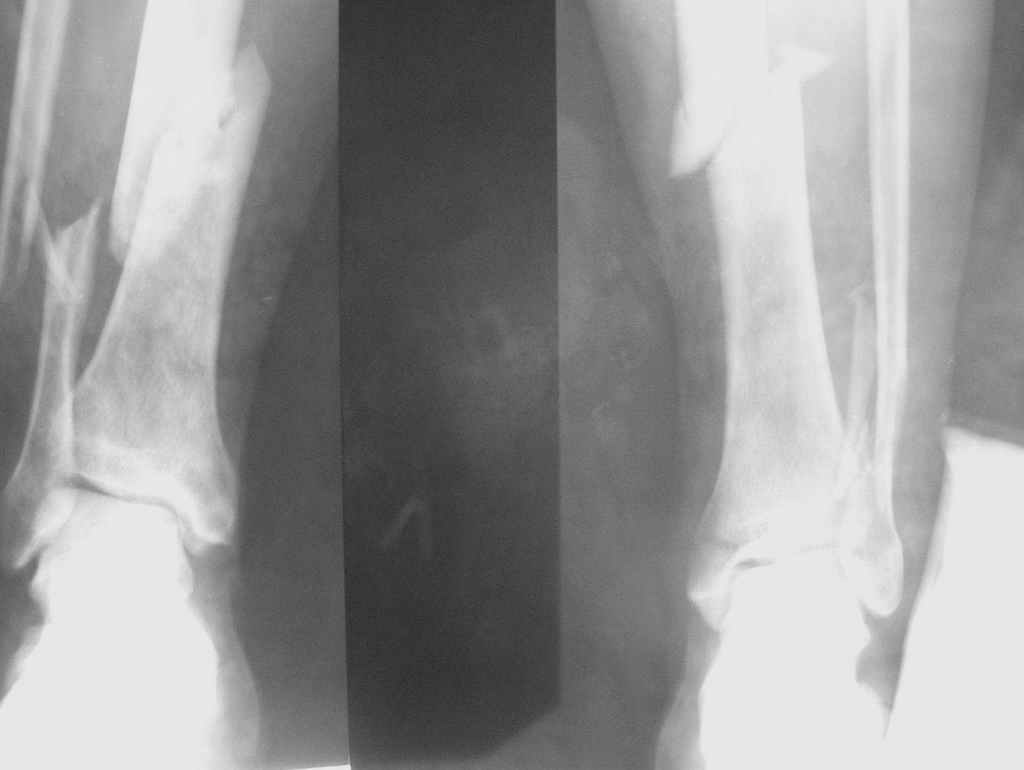

Уважаемые коллеги, у нас в Самаре в клинику травматологии мединститута доставили парашютиста с переломами голеней, причем справа перелом открытый.

В одной из больниц выполнили "классическую" первую помощь - якобы ПХО со швами и резиночкой в гипсовых лонгетах. К нам в клиникудоставлен на следующий день. 7 дней на вытяжении - состояние общее и со стороны раны стабильное. Посоветовавшись решили выполнить закрыто БИОС ChM. Сегодня оперировали. Получилось закрыто. Область открытого перелома дополнительно дренировали вакуумными дренажами.

Проблем с закрытой репозицией ожидать неоткуда - срок после травмы небольшой, переломы диафизарные.

Выглядит все неплохо. Хотя при свежих переломах запирать надо бы статически. И голеностопные суставы прицельно бы посмотреть.

Коллеги вечер добрый!А не сломана ли внутренняя лодыжка слева?А справа щель г\стопа какая-то клиновидная(а может мираж?:)) И зачем вакуум-дренаж?Какие задачи он решает??? Уж если были показания к дренированию,то по-моему следовало ставить проточный дренаж.И как там стопы,пятки,позвоночник?парашютист же!!!

2. Слева похоже на нестабильное повреждение г\стопного сустава (на первичных снимках, на

послеоперационных - срезано), хотя судить надо по клинике. сделайте нагрузочный тест (варус-вальгус.